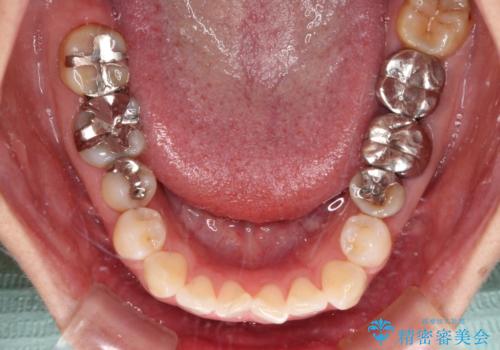

- 上下前歯のデコボコを気にして来院された患者様です。

カウンセリングにて詳しく話を聞いたところ、一番気になっているのは下顎前歯の叢生であり、上顎犬歯はあまり気になっていないとのことでした。

矯正治療は、歯の後戻りを抑制するために、治療終了後も保定装置をしっかりと使用していただくことが必須であるため、気になっている下顎だけを整えることで、その負担を半減できると考え、下顎のみの部分矯正として治療を行うこととしました。

装置としては、叢生の程度が強くなかったため、インビザラインの廉価版であるモデレート・パッケージを使用することとしました。

当院では治療前の歯列が整っていない限り、下顎前歯の舌側をワイヤーで固定するようにしています。下顎のみの部分矯正としたことで、マウスピース保定の負担を軽減することができました。